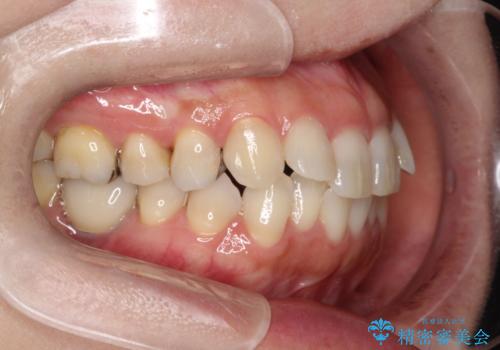

- 前歯のがたつきを主訴に来院されました。

なるべく目立たない矯正をご希望されたので、インビザラインにて治療することとなりました。